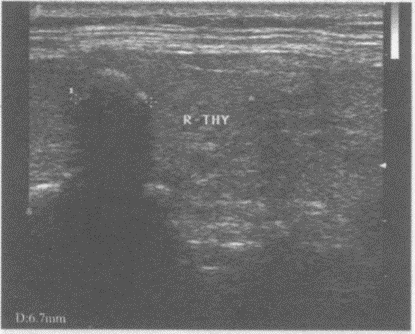

患者全身骨关节疼痛,有肾结石病史。行超声检查甲状腺,如图。最可能的诊断为()。

A.甲状腺腺瘤

B.甲状腺癌

C.甲状旁腺腺瘤

D.甲状腺囊肿

E.以上均不是